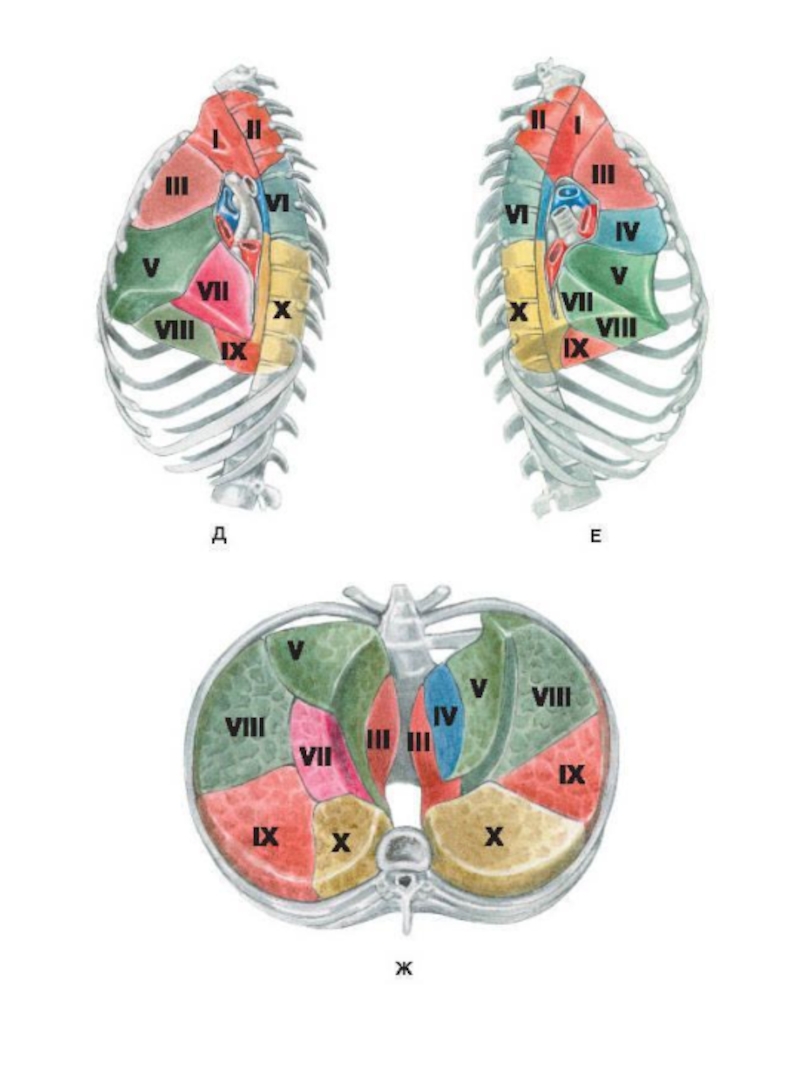

Анатомические изображения сегментов легких различных животных

Раздел: Другие животные